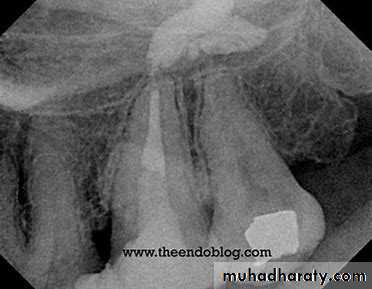

That includes some extension toward the pulp.

A liner such as Ca(OH)2 should be applied on the pulpal and axial walls.

On top a cement base is placed such as ZPHC or PCC, or modified ZOEC then a varnish is used to coat the walls.

Recently, new protocol prefers the use of dycal with GIC base, because of the present of chemical bonding between the tooth and the GIC that will reduce microleakage and the sensitivity postoperatively.

Deep Cavity